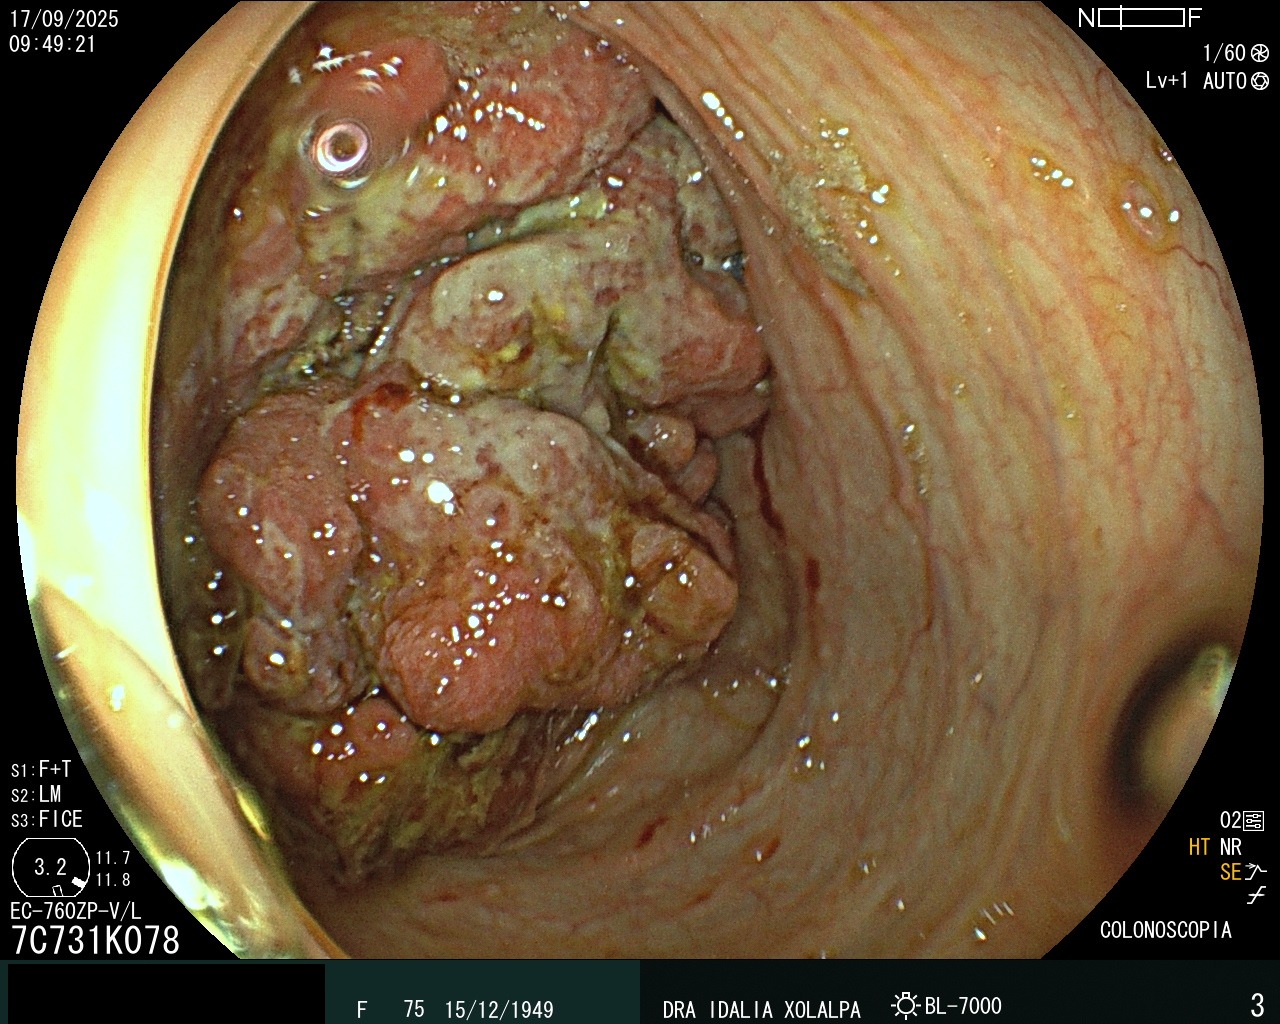

Tumor de Colon